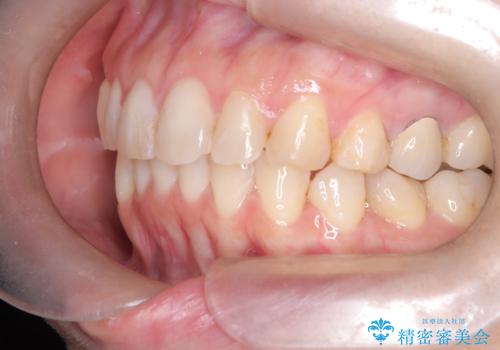

- 下の前歯のデコボコ(叢生)を気にされてご来院されました。精密な検査の結果、下の前歯を並べるスペースが不足していることが判明。患者様のご希望から、透明で目立ちにくい**インビザライン(マウスピース矯正)による治療計画を立案しました。主に歯の側面をわずかに削るIPR(歯間乳頭保護下ストリッピング)**などでスペースを確保し、下の前歯の叢生を解消することを目指します。

今回の矯正治療では、透明なマウスピース型の装置インビザラインを使用しました。目立たず、取り外しが可能なため、日常生活にほとんど影響なく治療を進めることができました。治療は、緻密に計算された計画に基づき、IPRなどで必要なスペースを確保しながら、下の前歯をスムーズに移動。これにより、長年の悩みであった下の前歯のデコボコが解消され、清掃しやすい、整った歯並びを獲得していただけました。